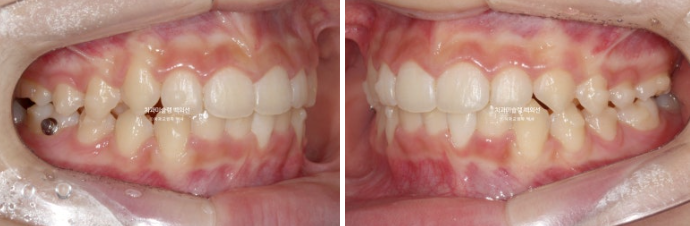

24년 2월부터 9월까지 장치를 모두 낀 후 모습입니다.

24.09

중심선이 아직 맞지는 않지만 과개교합이 해소가 되었습니다.

어금니 교합이 아직 완벽하진 않습니다.

배열은 좋습니다.

중심선, 교합 개선을 위해 추가장치 제작에 들어갔습니다